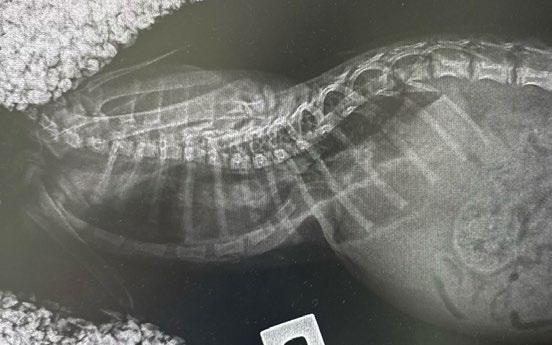

Four weeks later, Hotch was presented with marked lameness and a firm marked swelling of his left antebrachium. There were no obvious wounds or scabs, although he was hyperthermic. He was admitted for radiographs (see images) under sedation (dexmedetomidine 5µg/kg, methadone 0.3 mg/kg).

1

Radiographs showed signs of acute suppurative osteomyelitis, likely bacterial. This has a characteristic appearance in kittens, as the periosteum is not so strongly attached to the bone cortex, and the neutrophilic exudate lifts the periosteum, which then makes a florid new bone response ( blue arrow). Usually, these infections arise after a bite wound. The periosteal new bone formation is florid. Patchy portions of cortical bone lysis (yellow arrow) are also evident towards the centre of the lesion. At this stage we contacted Dr Richard Malik at the CVE as I had never seen anything like this before. Richard was also concerned about mild nutritional secondary hyperparathyroidism (NSH) due to the bone cortices appearing pale (osteopaenic), with an area of increased relative radiodensity immediately next to the growth plates (orange arrow). In NSH, the only normal bone is that laid down by endochondral ossification at the growth plates (and in this case—where new bone is laid down to wall off the infected bone), the rest of the skeleton is being broken down by osteoclasts under the direction of PTH.

Figure 1. Radiographs of the affected limb at presentation